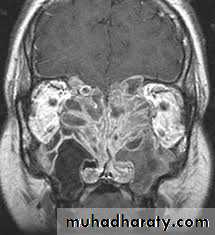

Investigation

4. CT- scan of the sinuses may show

microcalcification of opaque fungal mass in the

non-invasive form due to accumulated heavy

metals, e.g. calcium, manganese. There may be

evidence of bone expansion. The invasive type,

however, will show evidence of bone destruction

with spread of disease outside the sinuses. MRI

scanning may further help delineate fungal mucin

from reactive inflammation .